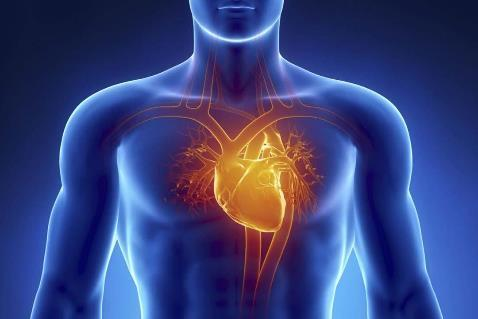

Heart Scans

Heart scans are a non-invasive method of detailing the presence, location and extent of calcified plaque build-up and coronary artery narrowing. Using safe amounts of radiation (comparable to two chest x-rays), heart scans can reveal risk factors for heart disease or a heart attack by providing a picture of your heart and its adjacent blood vessels.